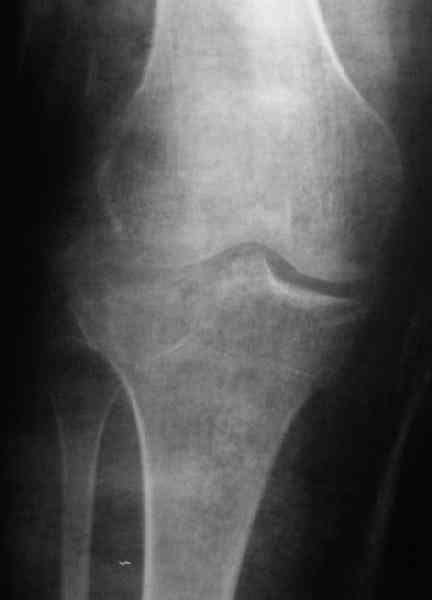

Обратился больной 46л. 3-месяца назад в каком-то городке Дальнего Востока упал с высоты, сделана Р-графия, наложена гипсовая повязка, от предложенной операции отказался и уехал домой, дальше где и как лечился, не говорит.

Ходит при помощи двух костылей, жалобы на боли при нагрузке, в покое и при движении, без нагрузке боли нет, разгибание 175 гр, сгибание 90 гр, симптомов повреждения связочного аппарата к/с не определяется, от предложенного артродеза пока отказывается.

По тактике лечения, более импонирует второй вариант, но наружная плато расколота и туда при нагрузке внедряется н/мышелка бедра, поэтому после дистракции как репонирвать: или стяжными винтами, или изогнутами спицами или субхондральная костная пластика?

У пациента основной проблемой является импрессионый перелом наружного мыщелка, уже неправильно сросшийся, по-видимому. Аппаратом закрыто можно только подправить угол на уровне метадиафиза. Что

улучшит разве что внешний вид конечности, но не решит основной проблемы - грубой деформации суставной поверхности.